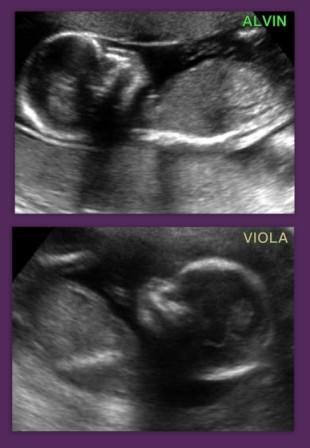

fra 5 uger: konstatere liv og antallet af fostre

11 uger, 4 dage - 13 uger, 6 dage: Nakkefoldskanning,

18 - 22 uger: Misdannelsesskanning,

26 - 28 uger: 3D/4D skanning, (kan udføres fra 9 uger og op til fødsel),